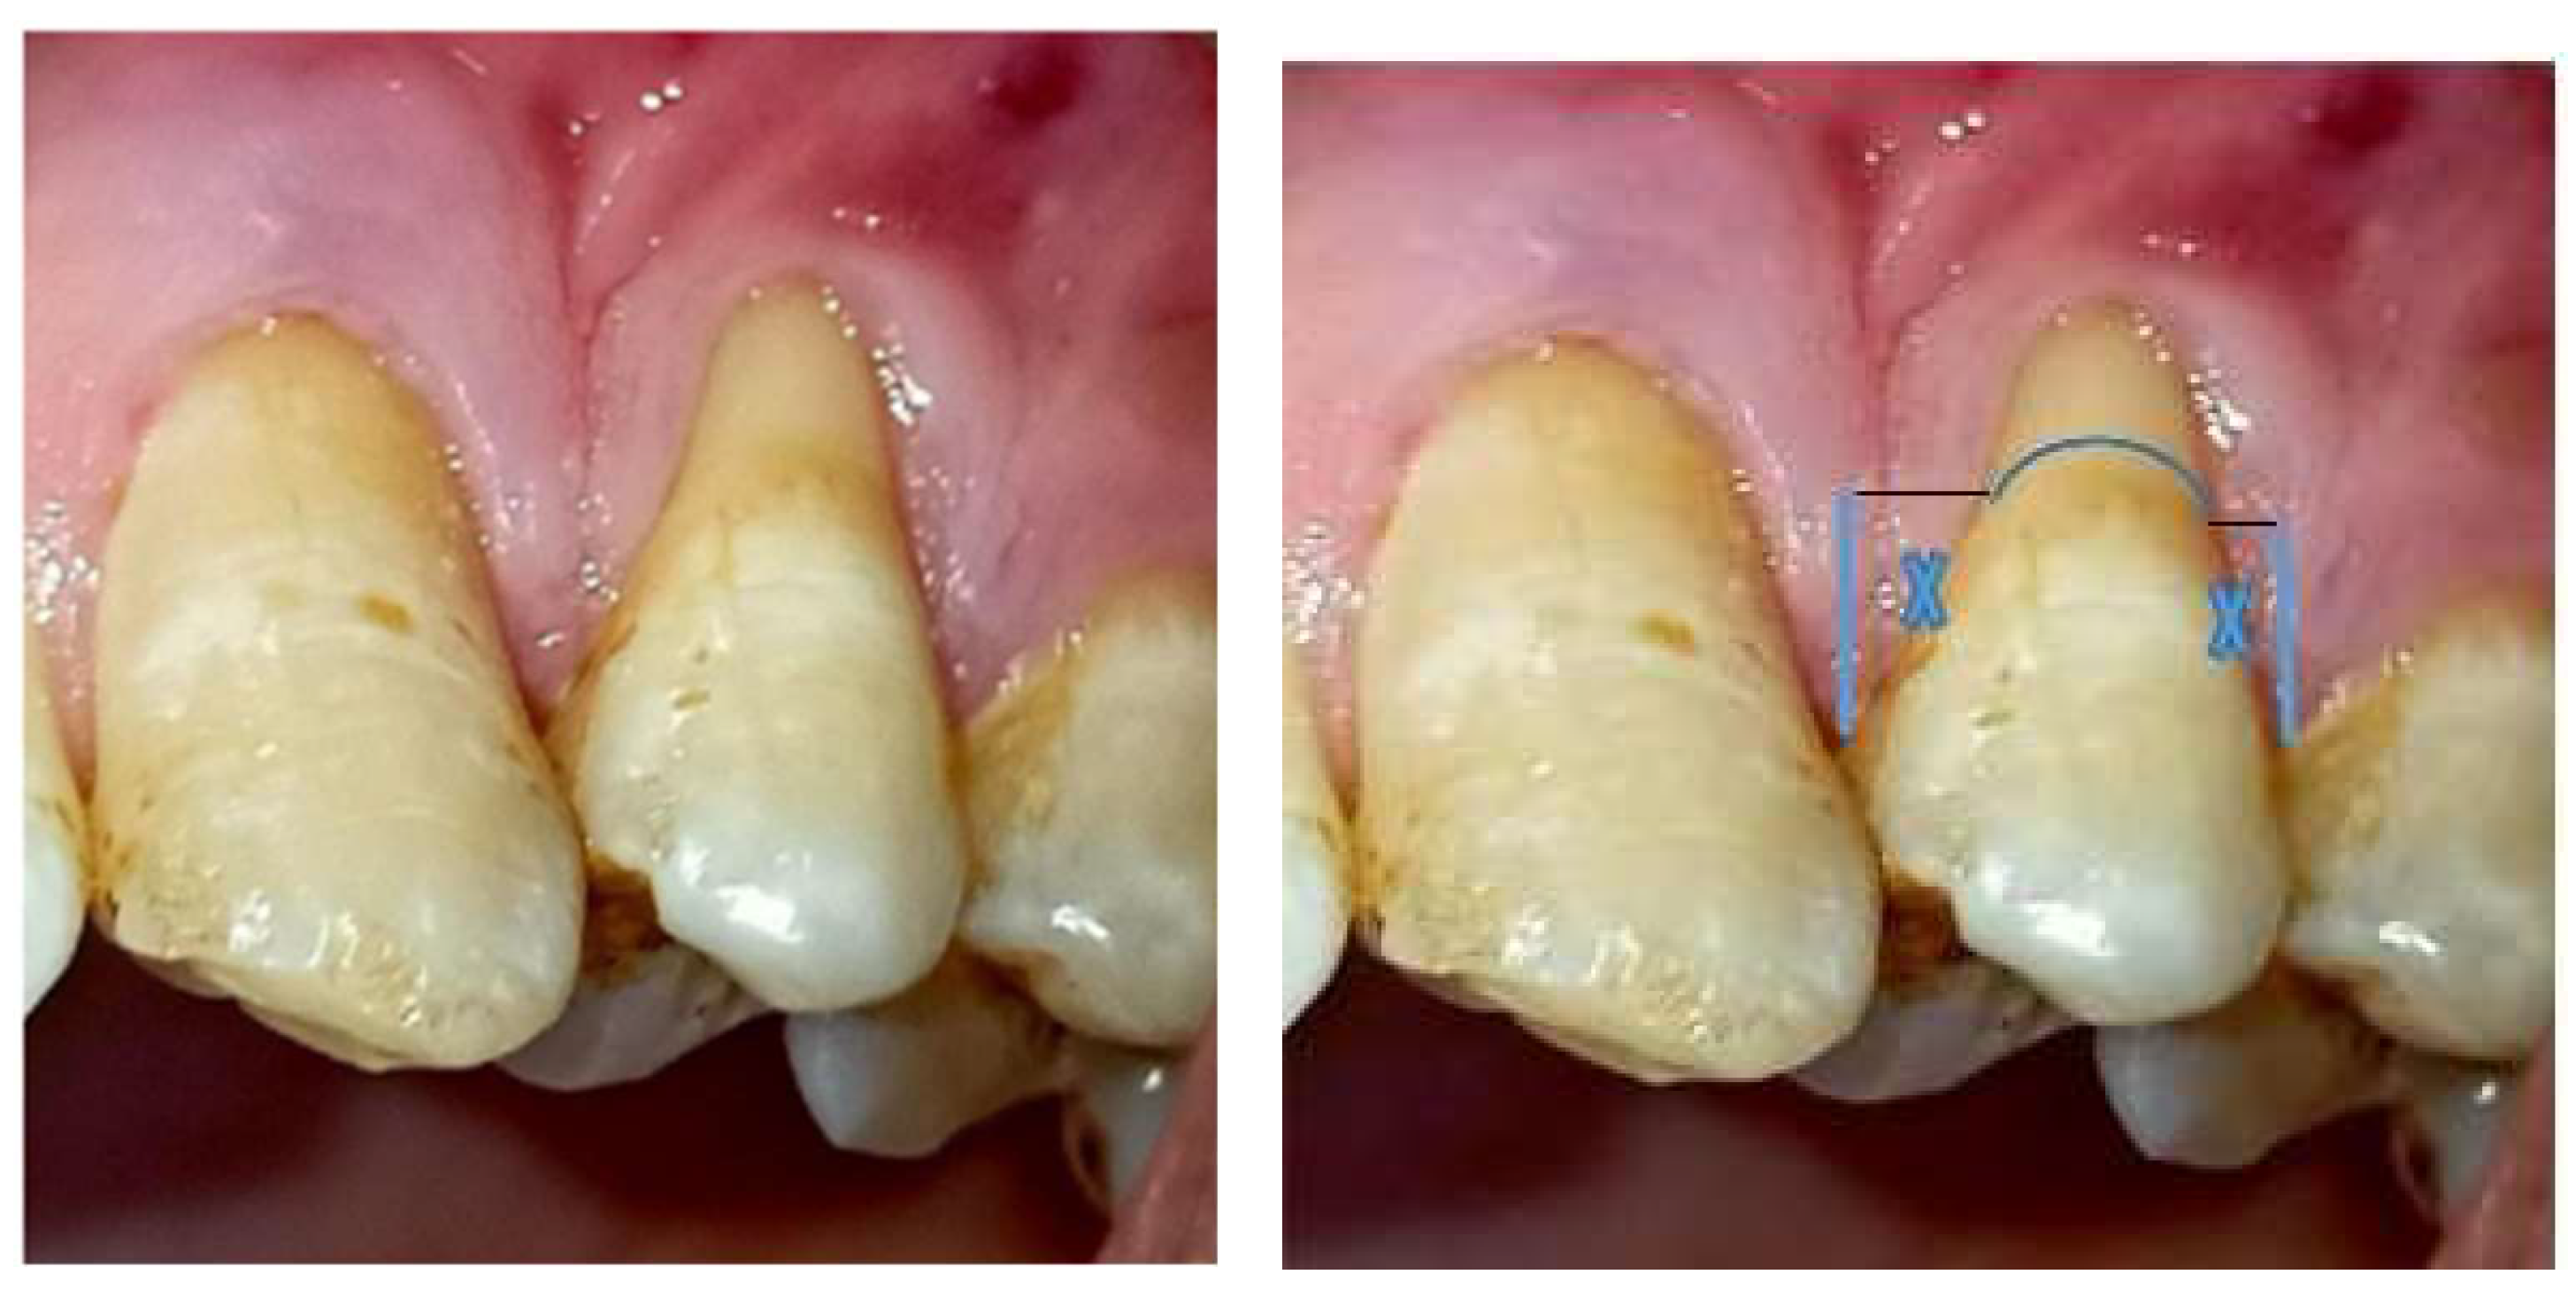

Figure 1. clinical photograph showing 41years old male patient, has GR miller cl(IIa) at upper left first premolar. In a nonrotated tooth with no interproximal attachment loss and with intact papilla height. the ‘deal papilla height (X) coincides with the anatomical papilla height.

A single-stage treatment approach was planned, all selected patients received a comprehensive periodontal examination and oral hygiene instructions, and they were subjected to full-mouth scaling and root planning. After 30 days, reevaluation was performed, which clinical improvement of clinical parameters (Figure 1). A coronal advancement flap with connective tissue graft was planned and performed to treat the gingival recession to increase the amount of keratinized tissue.

The rationale for the surgical technique begins with determining the maximum root coverage (MRC). This involves calculating the optimal height of the anatomical interdental papilla. For teeth affected by gingival recession, the ideal height is the apical-coronal dimension of the interdental papilla necessary for complete root coverage. For non-rotated and correctly aligned teeth, this height is measured on the tooth itself. For rotated or misaligned teeth, the measurement is taken from the corresponding contralateral tooth. The process of measuring the anatomical papilla height includes assessing the vertical distance between two teeth and the horizontal line from the cementoenamel junction (CEJ) of the tooth to the tip of the papilla. In a healthy periodontium with a non-rotated tooth, the papilla tip is aligned with the contact point, which helps in predicting the potential for root coverage. The optimal height is the distance from the mesial-distal line angle to the contact point of the tooth. This line angle is identified by elevating the interdental soft tissues to expose the interdental CEJ. After determining the ideal papilla height, it is marked apically from the mesial and distal tips of the papillae of the recessed tooth. Horizontal projections from these marks to the edge of the recession define two points, which are then connected by a scalloped line to establish the 'line of root coverage [10].